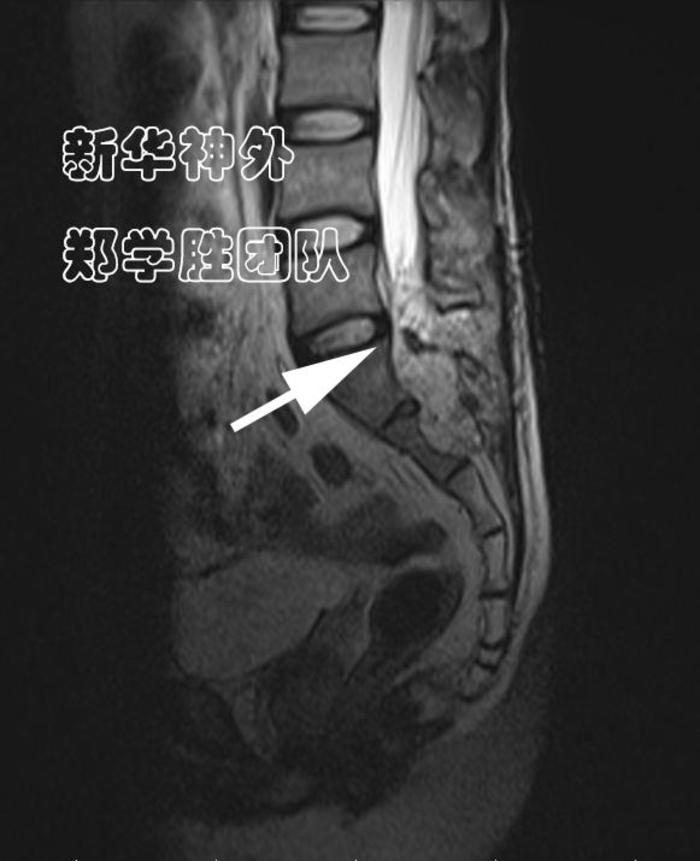

术前MRI显示:8cm巨大腰骶管囊肿;

水往低处流,难道漏口在腰5上段吗?

经过仔细读片,郑学胜主任判断,骶管囊肿漏口很可能在腰5骶1间隙(箭头所指),而不是在腰5上段。